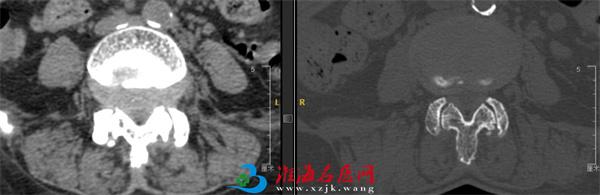

术前资料

入院后,在完善相关检查后王阿姨被诊断为:腰椎管狭窄、腰椎不稳、腰椎间盘突出。随后脊柱外科尚军、张冶手术团队在骨科机器人+3D裸眼显微镜的辅助下,为王阿姨进行了腰椎后路减压+内固定+椎间融合术 (L4/5)。